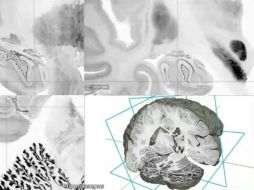

Tecnología Presentan modelo de cerebro humano en 3D y alta resolución 20 de junio de 2013 - 20:16 hs Ciencia Cerebro